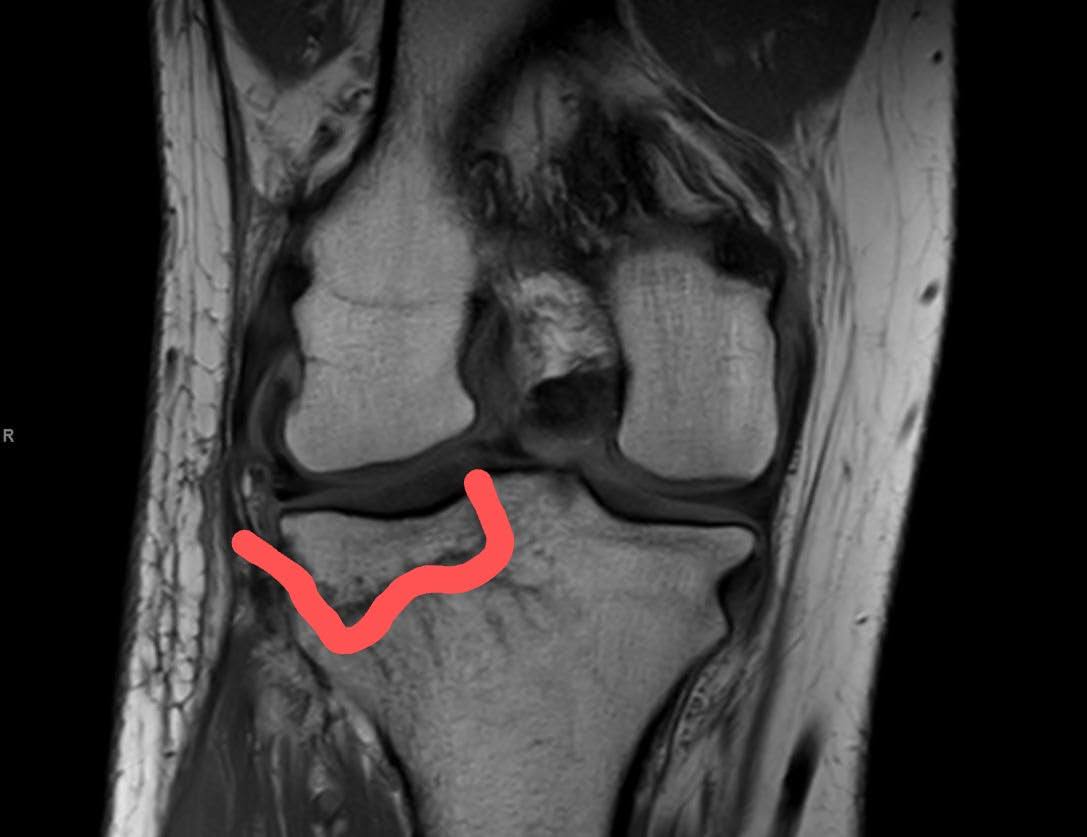

I was referred to an Orthopedic Surgeon who confirmed with MRI (imaged below) that both legs were fractured. On Thursday 08/06/2020, I went into surgery and had three screws placed in each leg, holding the fracture together to heal faster.